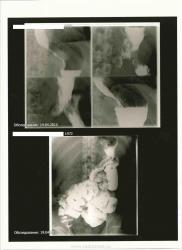

Уважаемый коллега, всегда важна конкретика: какие жалобы конкректно, какие операции ? и по поводу чего? По представленным снимкам- поддержу пост Анатолия Владимировича- впечатление, о дефекте в субкардиальном отделе желудка по малой кривизне: suspicio cr кардиального отдела желедука.Рекомендована КТ брюшной полости.

Тот бугристый дефект в кардии- состояние после избыточной фундопликации, симулирует опухоль. В остально - "жертва перенесенных операций"...